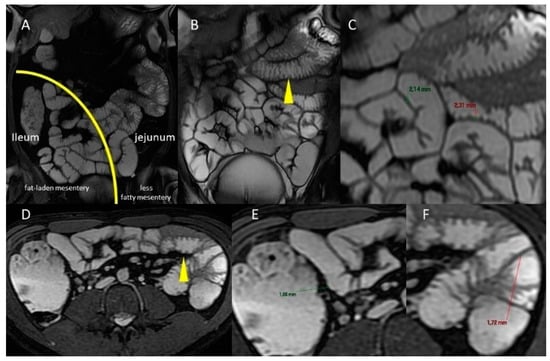

2. Macroscopic Anatomy Features of Small Bowel